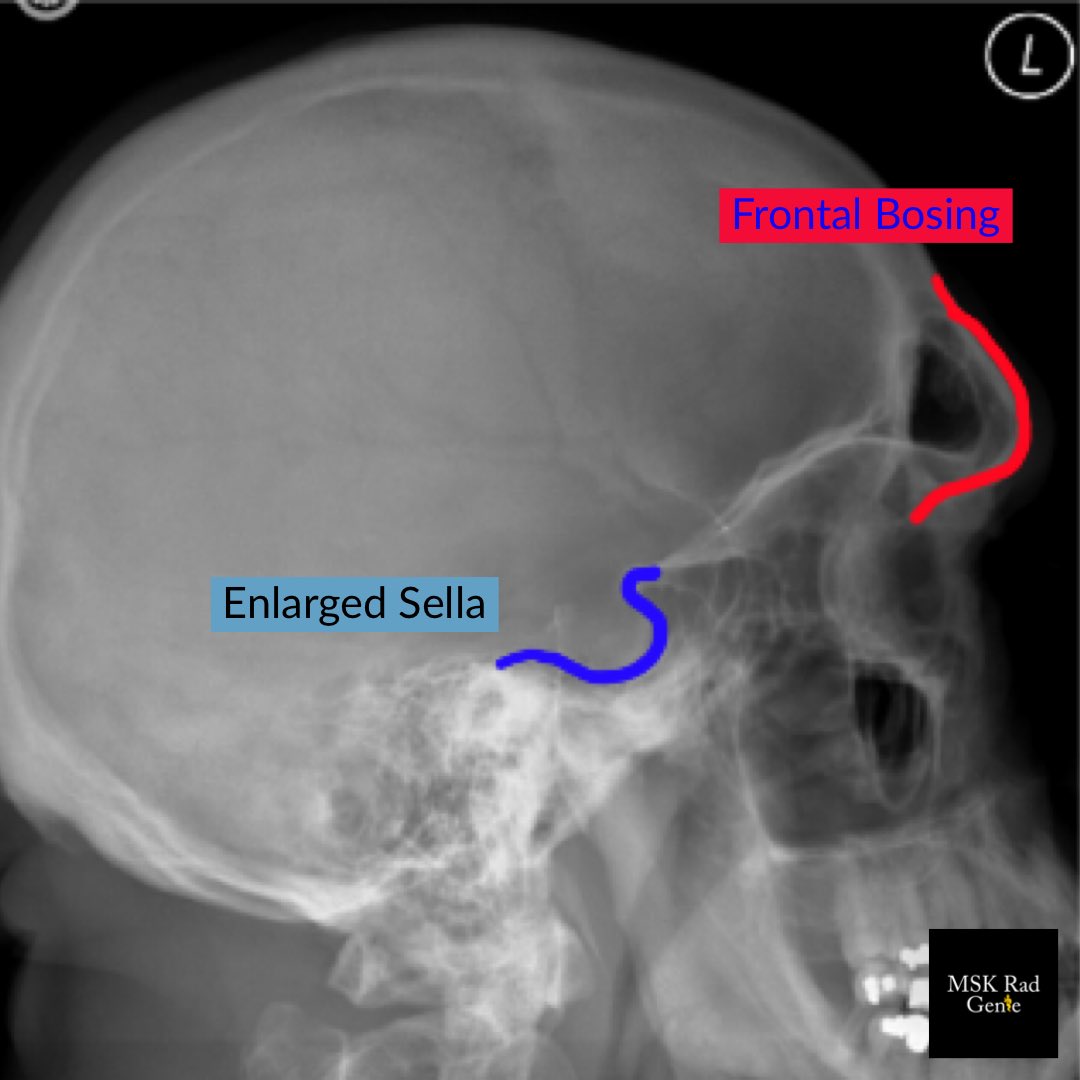

Typical MSK imaging findings in Acromegaly: 1. “Spade” hand distal phalanges 2. Frontal bossing 3. Enlarged sinuses 4. Widened joint spaces 5. Thickened heel fat pad (>2.5cm)

#RadRes#MSKRadpic.twitter.com/R3uLKomBnb